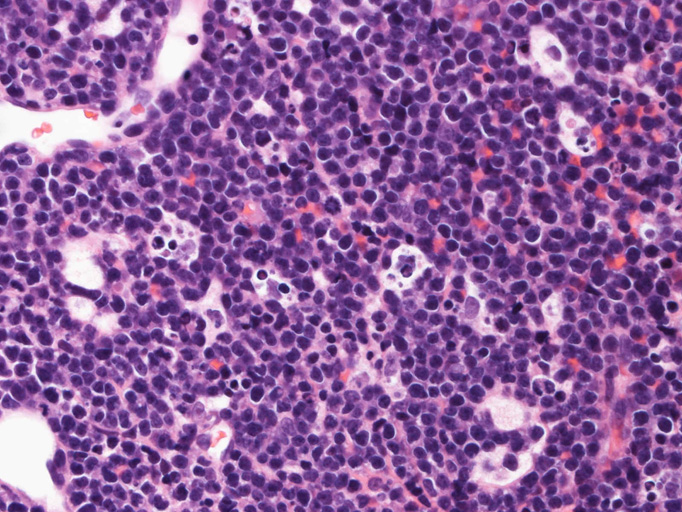

エコーガイド下肝腫瘤針生検組織

尾状葉の腫瘍から16G, 11mm穿刺針で5mm, 2mmの組織を採取した。2mmの組織は線維組織と肝組織で腫瘍細胞を含んでいなかった。穿刺針洗浄液をkaryotypeに提出する。